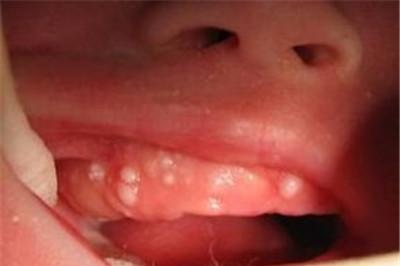

马牙是指大多数婴儿在出生后4~6周时,口腔上腭中线两侧和齿龈边缘出现一些黄白色的小点,很象是长出来的牙齿,俗称“马牙”或“板牙”。

宝宝马牙是米粒大小的白色或者黄白色颗粒状,一般没有不适感,个别婴儿可出现爱摇头、烦燥、咬奶头甚至拒食,这是由于局部发痒、发胀等暂时不适引起的,一般不需做任何处理。

马牙不是病,它是牙齿发生过程中伴发的现象,并不是人人都长。婴儿吮奶过程中牙床和乳头摩擦,经过一段时间后“马牙”便会自行脱落。